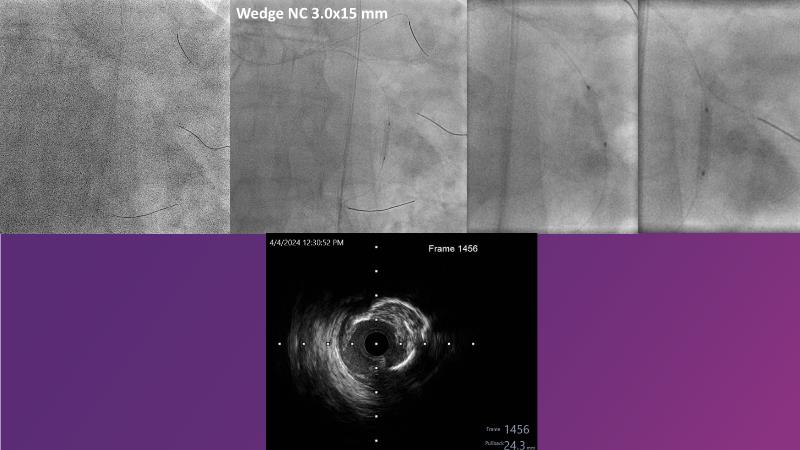

Don't miss this session for expert guidance on preparing and managing complex lesions. Gain insights into choosing the right tools, including microcatheters and balloons, for optimal treatment outcomes. Explore the innovative features of flagship devices for complex PCI, and Pronavi microcatheter and Alveo HP CTO balloon to treat complex CTO lesions. Learn about the safety and efficacy of the Wedge NC scoring balloon, the importance of using POT dedicated balloons in POT and DOT techniques, and get updated tips and tricks from ongoing clinical practices.

- To gain insights on Pronavi microcatheter and Alveo HP CTO balloon to treat complex CTO lesions, understand the safety and efficacy of lesion preparation with Wedge NC scoring balloon and the significance of using POT dedicated balloon in POT and DOT technique